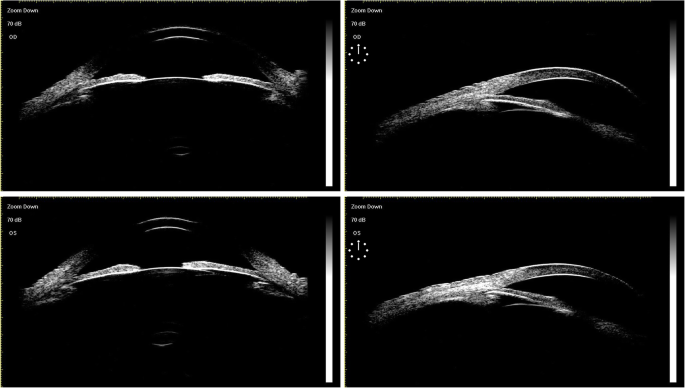

The patient is a 63-year-old male who was diagnosed with chronic angle-closure glaucoma and accepted UCP in another hospital on both eyes 4 months ago. We asked the hospital for the preoperative data of the patient. The visual acuity was 20/160 (OD) and 20/40 (OS), and the best-corrected visual acuity (BCVA) was preserved at 20/100 (OD) with + 0.50D/− 1.50D*10 and 20/25 (OS) with + 0.75D/− 1.50D*165. The patient presented with bilateral cataract (C2N2P1 OD, C2N2P1 OS) according to Lens Opacities Classification System III (LOCS III). The optic discs of both eyes were pale with C/D = 0.9 (OD) and C/D = 0.8 (OS), respectively. The ultrasound biomicroscope (UBM) data were as follows: The iris of both eyes was swollen and the anterior chambers were narrow. In the right eye, the vertical anterior chamber depth was 2.24 mm and the corresponding sulcus-to-sulcus distance was 12.11 mm, and the horizontal anterior chamber depth was 2.28 mm with the corresponding sulcus-to-sulcus distance of 11.80 mm. In the left eye, the vertical anterior chamber depth was 2.26 mm and the corresponding sulcus-to-sulcus distance was 11.98 mm, and the horizontal anterior chamber depth was 2.24 mm with the corresponding sulcus-to-sulcus distance of 11.90 mm. Visual field examination showed that the right eye had a tubular visual field and the left eye had a peripheral visual field defect. Under the situation of using three kinds of anti-glaucoma drugs (methazolamide, carteolol hydrochloride, and brinzolamide), the baseline intraocular pressure (IOP) was 30 mmHg (OD) and 31 mmHg (OS), respectively. The preoperative anterior segment image (Fig. 1) showed that pupils of both eyes were regular circular and the depth of the anterior chamber was normal. The preoperative UBM image (Fig. 2) presented that the anterior chamber angle of both eyes was closed, the lens position was normal without deviation, and the anterior capsule was smooth without adhesion.

Postoperative UBM image of UCP: The central anterior chamber depth is about 2.32 mm (OD) and 2.25 mm (OS), respectively. The anterior chamber angle was closed in all directions and the ciliary body displaced forward to the root of the iris in both eyes. The shape of the superior suspensory ligament is irregular in the left eye. Both lenses show enhanced echo. There exists an adhesion in the anterior capsule periphery in both lenses while the lens position of the right eye deviates